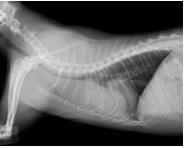

幸いステロイドにより、減容積の効果が高く得られたので、そのまま外科手術にて腫瘍摘出術を行いました。

↑ステロイド服用後の胸部レントゲン